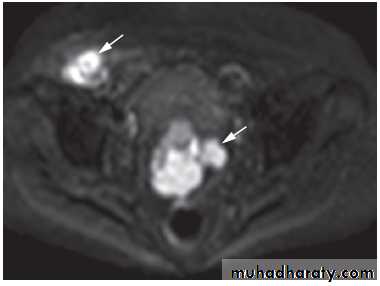

-The typical features of

polycystic ovaries on

ultrasound or MRI include

large volume ovaries

with multiple small

follicles arranged

around the periphery,

forming the appearance

of a ‘string of pearls’ .